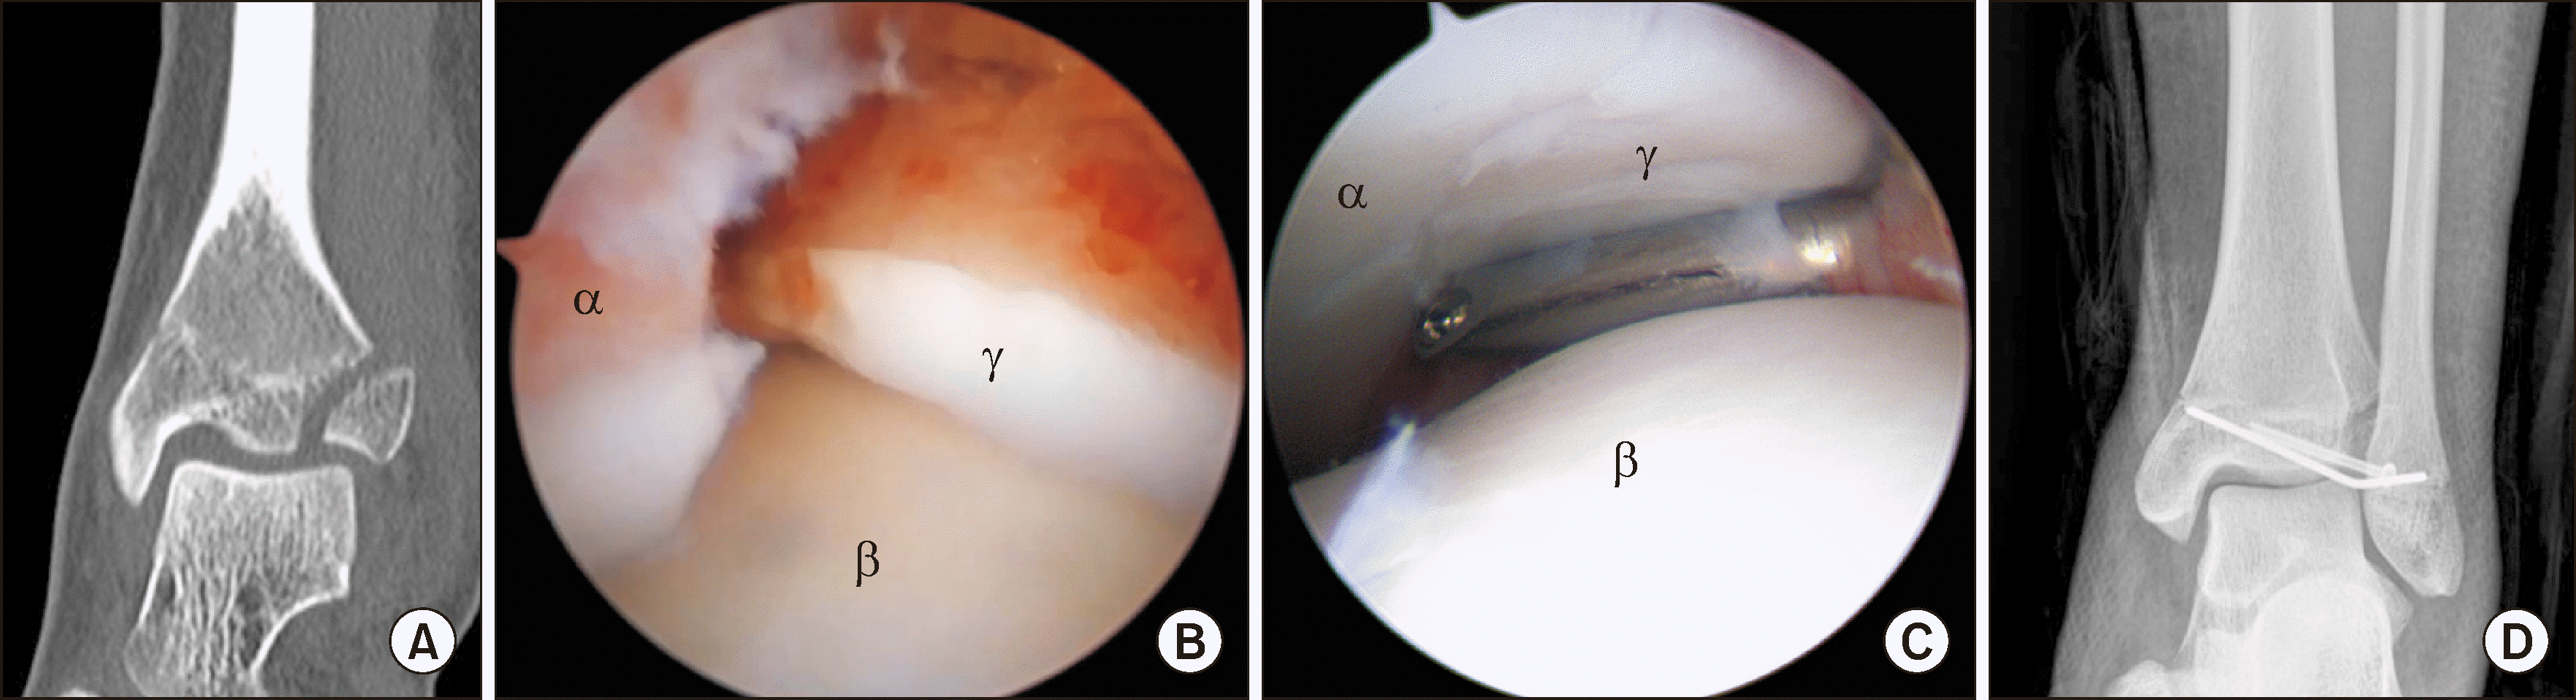

Figure 1

Anteroposterior (A) and lateral (B) radiographs shows Danis-Weber type C lateral malleolar fracture. Plain radiographs do not show obvious osteochondral lesions. Arthroscopy shows a loose body (C) and osteochondral lesion of the medial talar dome (D). αLoose body, βTibia, γTalus, δOsteochondral lesion.

Figure 2

(A) Arthroscopic findings in ankle fracture through the anteromedial portal show an osteochondral lesion of talus. (B, C) Arthroscopic microfracture was performed after debridement. αTibia, βTalus, γOsteochondral lesion.